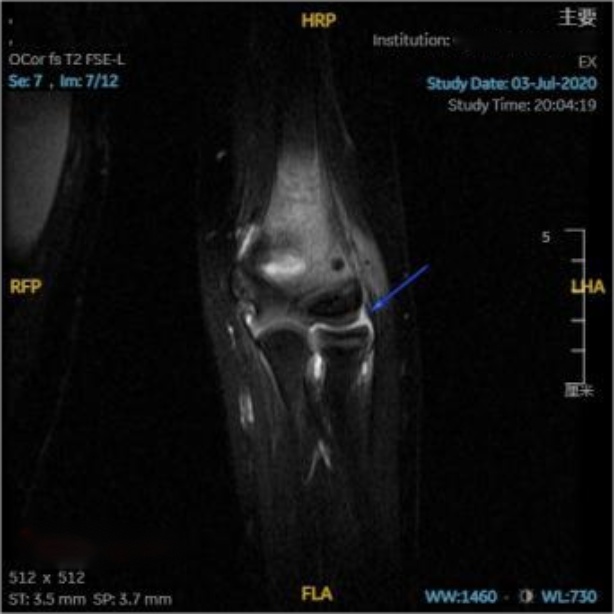

在对照MRI影像横断位,可见环绕桡骨头的环状韧带连续性完整,与桡骨头间充满高信号韧带下积液(见图3(a)图3(b)蓝箭头);在对照MRI影像冠状位(见图3(c)蓝箭头),可见关节腔内充满高信号的关节积液,积液内可见一明显低信号带状影,未见低信号影嵌入关节内,提示环状韧带连续性良好未嵌入肱桡关节内;在对照MRI影像矢状位(见图3(d)图3(e)蓝箭头),可见肘关节内有高信号的关节积液,关节间隙旁可见一低信号带状影,形状完整,连续性良好,并未嵌入关节间隙内。

放射学复位后,即复位后X片提示桡骨干轴线无明显偏离肱骨小头骨化中心,但患儿仍存在肘关节活动受限,此种情况即视为解剖学复位失败,其MRI影像表现为:横断位可见环状韧带局部变薄,与桡骨头之间可见高信号积液,韧带局部不再环绕桡骨头,与桡骨头交界处模糊(见图4(a)红箭头);冠状位可见环状韧带局部变薄,疑似连续性中断,脱套的环状韧带呈低信号,其上半部分卡压于肱桡关节间隙中,关节间隙内见带状液性高信号,关节周围可见软组织肿胀(见图4(b)红箭头);矢状位可更直观清晰的看到在关节间隙中的高信号关节积液衬托下,嵌入肱桡关节内的低信号环状韧带;除此之外也可见尺骨鹰嘴近端骨皮质信号不连续,断端间对位对线良好,整个左肘部周围肌肉均有广泛肿胀(见图4(c)红箭头)。